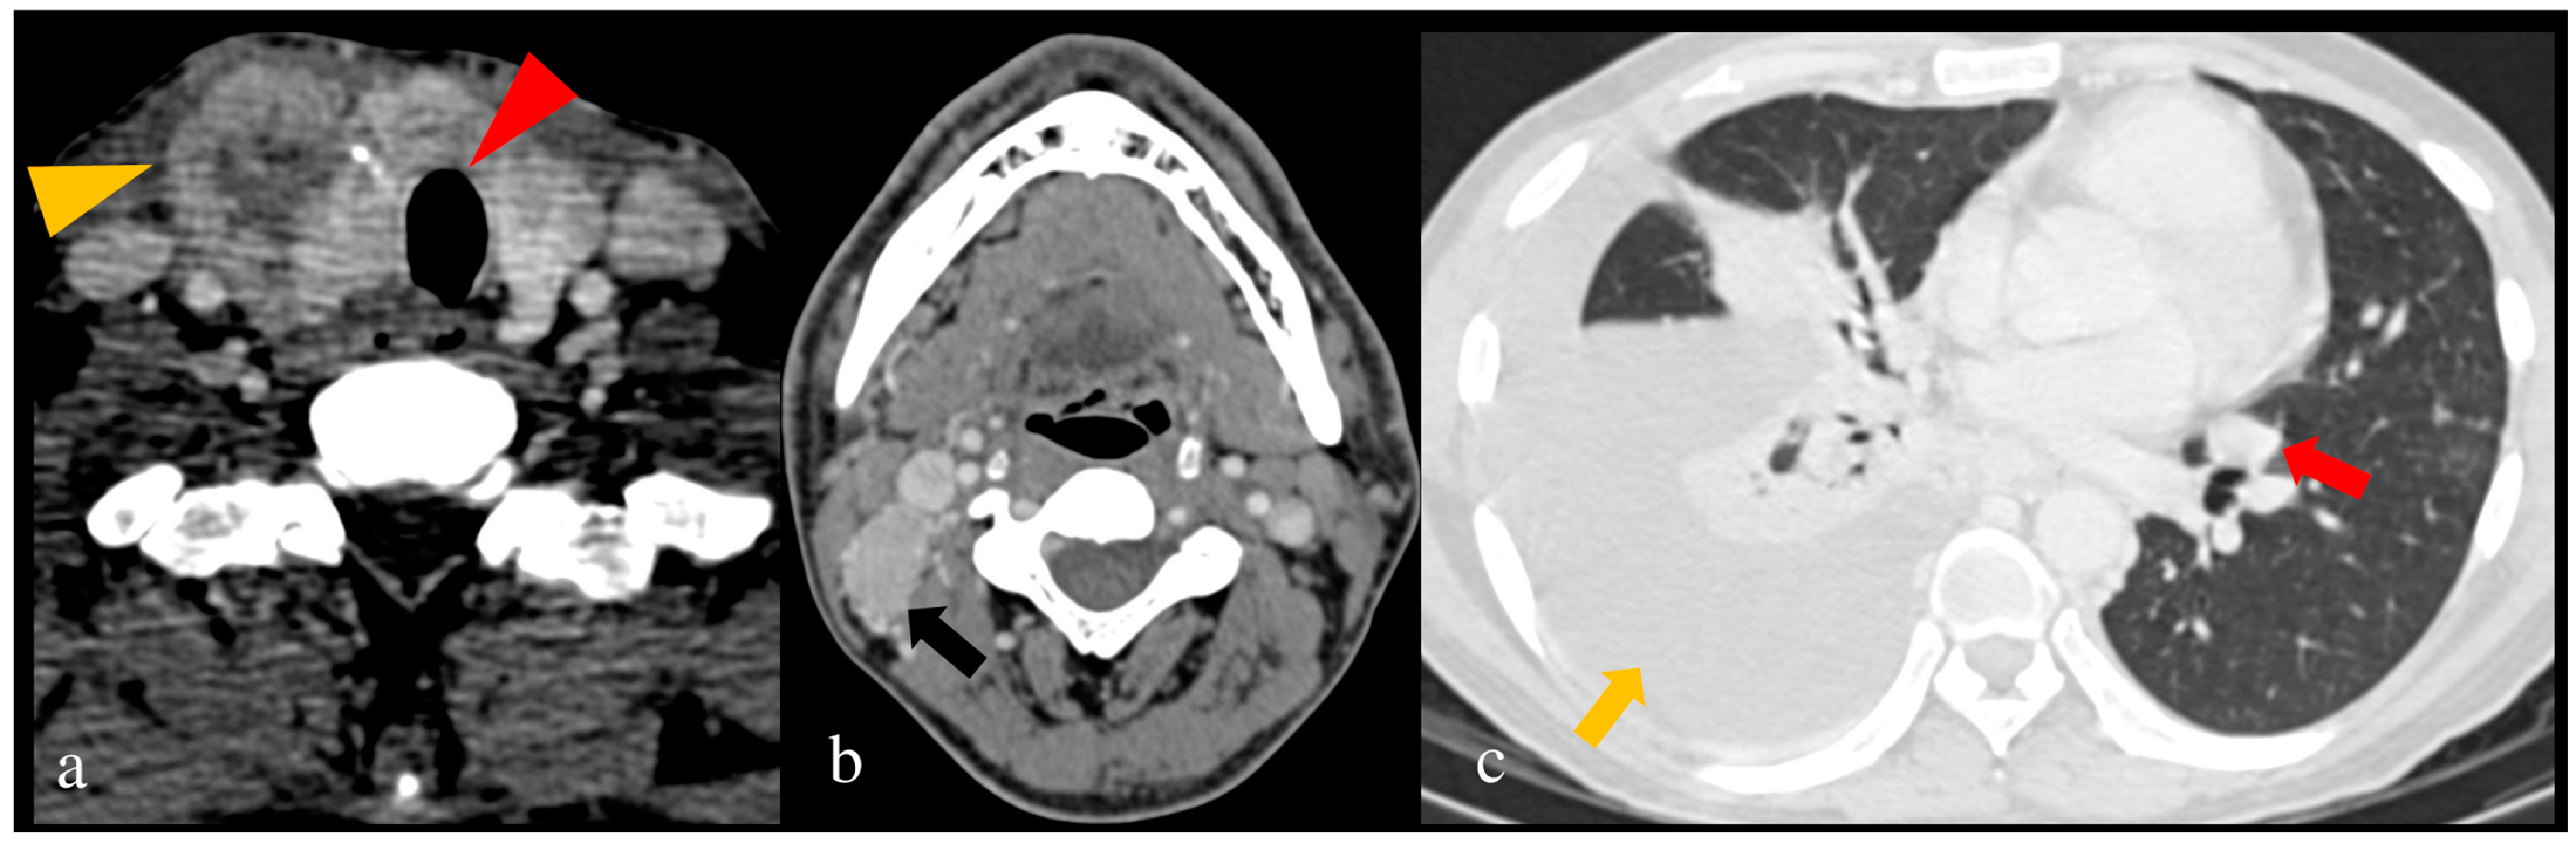

| Tracheal invasion as per SHIN grading (Figure 3) | -Total thyroidectomy with/without RAI -Grade 1: Shave procedure without any residual disease -Remaining grades: window resection/circumferential tracheal resection and re-anastomosis. |

- Mahajan, A.; Sable, N.; Vaish, R.; Chaukar, D.; Chaturvedi, P.; Pai, P. CT based modified SHIN classification for grading trachea Invasion: Addressing the resectability issues in Thyroid cancer. In Proceedings of the European Congress of Radiology-ECR 2019, Vienna, Austria, 27 February–3 March 2019. [Google Scholar]

- Seo, Y.L.; Yoon, D.Y.; Lim, K.J.; Cha, J.H.; Yun, E.J.; Choi, C.S.; Bae, S.H. Locally Advanced Thyroid Cancer: Can CT Help in Prediction of Extrathyroidal Invasion to Adjacent Structures? Am. J. Roentgenol. 2010, 195, W240–W244. [Google Scholar] [CrossRef]

| Seo et al. (2010) [76] | Diagnostic accuracy for ETE | 84 | CT | For tracheal invasion: S = 59.1%, Sp = 91.4%, A = 83.2% For esophageal invasion: S = 28.6%, Sp = 96.2%, A = 90.7% For invasion of CCA: S = 75.0%, Sp = 99.4%, A = 98.8% For invasion of IJV: S = 33.3%, Sp = 98.8%, A = 97.1% For invasion of RLN: S = 78.2%, Sp = 89.8%, A = 85.5% | Despite a low sensitivity, CT can be a valuable modality for ETE detection. |